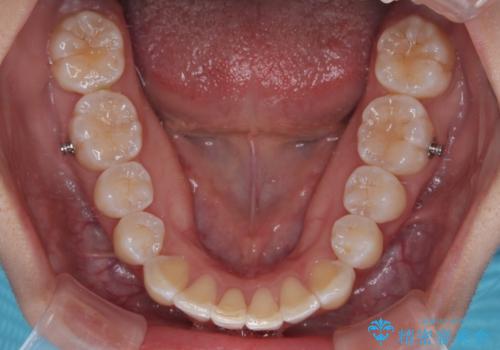

前歯のデコボコを治したい インビザライン矯正

- 上下前歯の叢生を気にして来院された患者様です。

インビザラインでの治療を希望されていて、デコボコの程度が中等度であり、安価なパッケージにて対応可能と判断されたため、インビザライン・モデレートを用いて矯正治療を行うこととしました。

インビザライン・モデレートは、製作できるアライナーの枚数に制限があるため、移動可能な量に限りがあるものの、インビザライン・ライトよりも枚数が多いため、幅広い症例に対応可能です。